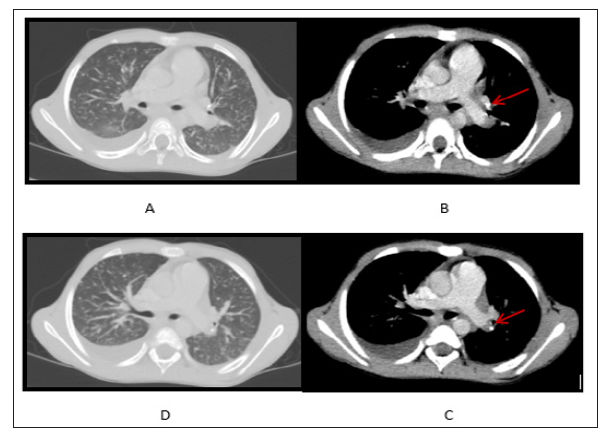

Gradual clinical deterioration started since the end of May 2015, when high temperature, loss of weight, headache, abdominal distention, and pain in multiple joints appeared. Abdominal examination in the middle of June revealed ascites, hepatomegaly, splenomegaly, enlarged up to 1-5 cm in size mesenteric lymph nodes. Computed tomography (CT) of the lungs revealed pleural collection in the right haemithorax, nodular shadows in both lungs, small calcifications in left bronchopulmonary lymph nodes (Figure 1). Blood count analysis demonstrated hypochromic anaemia, blood biochemistry showed increased CRP up to 38mg/L. T-SPOT. TB test was positive on June 26, 2015. Mbt DNS by Xpert® MTB/RIF (Cepheid, Sunnyvale, CA, USA) was positive in low concentration without resistance to Rifampicin from gastric aspirate sample on June 26, 2015. Skeletal scintigraphy revealed arthritis in hip, knee and pedal joints, showing deterioration comparing with previous examination

Figure 1: (A,D) Nodular shadows in lung parenchima and pleural collection in the right haemithorax; (B,C) Calcified bronchopulmonary lymph nodes (arrows).

Our patient developed severe TB during 8 months of the treatment with adalimumab, despite the fact that LTBI and TB disease were excluded before therapy. Taking into account the densely calcified lymph nodes identified on CT, one can speculate, that TB infection was old, acquired in the past, and not diagnosed by conventional screening methods prior treatment with adalimumab. It has been shown that CXR can have low-sensitivity and specificity in detecting TB abnormalities. Chest CT is superior to CXR in the visualization of intrathoracic lymphadenopathy, mild parenchymal abnormality and early cavitation [9]. CT scans in addition to CXR revealed calcification in lymph nodes and lung parenchyma in 42% of children and adolescents diagnosed with TB in study by Ziemele et al [10]. Thought old calcified TB lesions are uniformly negative for culture and acid fast- staining, such lesions are frequently found in lungs in reactivation TB indicating their association with reactivation. In the study by Iida et al. [11], it was shown that old TB foci, particularly those exhibiting some calcification, all were negative for culture and acid-fast staining, however contained abundant Mbt components.